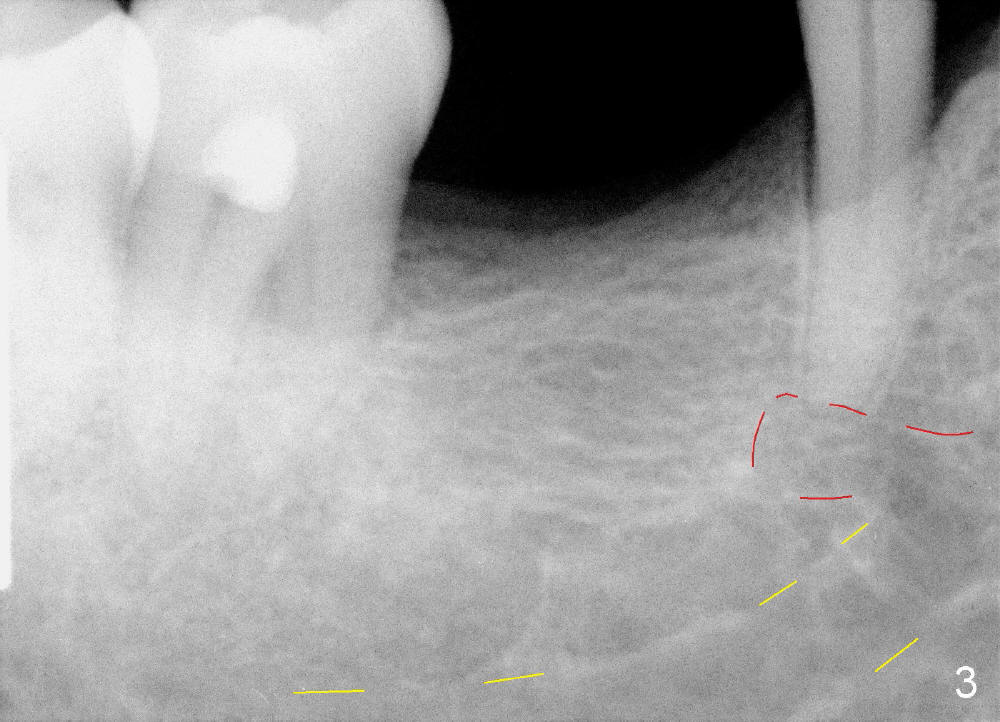

It is critical to identify the inferior alveolar canal (IAC) prior to and during implantation. A 59-year-old man requests implant for the lower right 1st molar (Fig.1). PA taken with a regular sensor holder does not show IAC except part of the mental loop (Fig.2 red dashed line), whereas the one taken with an endo sensor holder does show IAC (Fig.3 yellow dashed line).

When a positioning pin is placed in the osteotomy with 10 mm deep, the sensor cannot be placed deep enough because of pin interference so no IAC is visible (Fig.4). When the pin is removed and the sensor is placed low enough, IAC is clearly shown, but the osteotomy is barely visible (Fig.5 pink dashed line). With information obtained from pre- (Fig.2,3) and intra- (Fig.4,5) op PA, twelve mm of osteotomy appears to be appropriate. A final implant (5.3x12 mm) is placed with separation from IAC (Fig.6, insertion torque 50 Ncm). A healing abutment is placed (Fig.7,8), which helps retain perio dressing (Fig.9). Two weeks later, the gingiva heals around the abutment (Fig.10). Four months postop, the implant appears to osteointegrate (Fig.11). A cemented abutment is placed (Fig.12). With supragingival margin, oral hygiene is easily maintained (Fig.13). Due to delayed placement, the gingival embrasure is extremely large (*). The issue is much less with immediate implant.